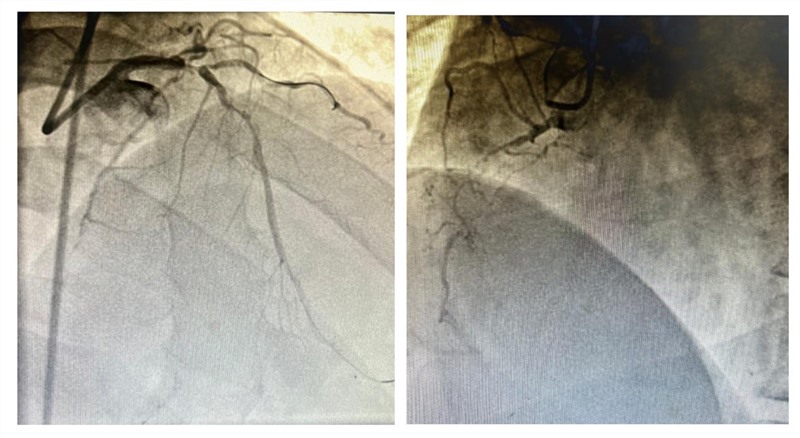

近日,由渝中心血管内科、重症医学科、血管外科组成的多学科(MDT)团队,历时7小时在ECMO支持下成功救治一例极高风险复杂冠脉病变的患者。患者男,48岁,本次因急性胸痛入住渝中心血管内科,确诊为急性非